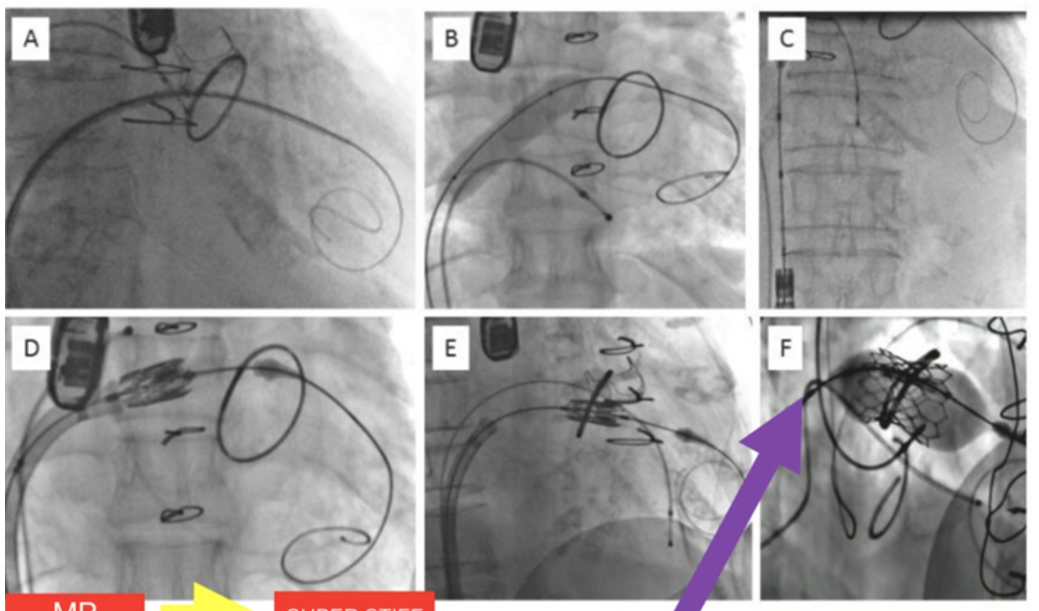

Passo a Passo do implante de VIV e VIR

(A) cruzamento para o VE - Agilis - super stiff (B) é dilatação do Septo. Prótese fica 1/4 a 1/3 no VE